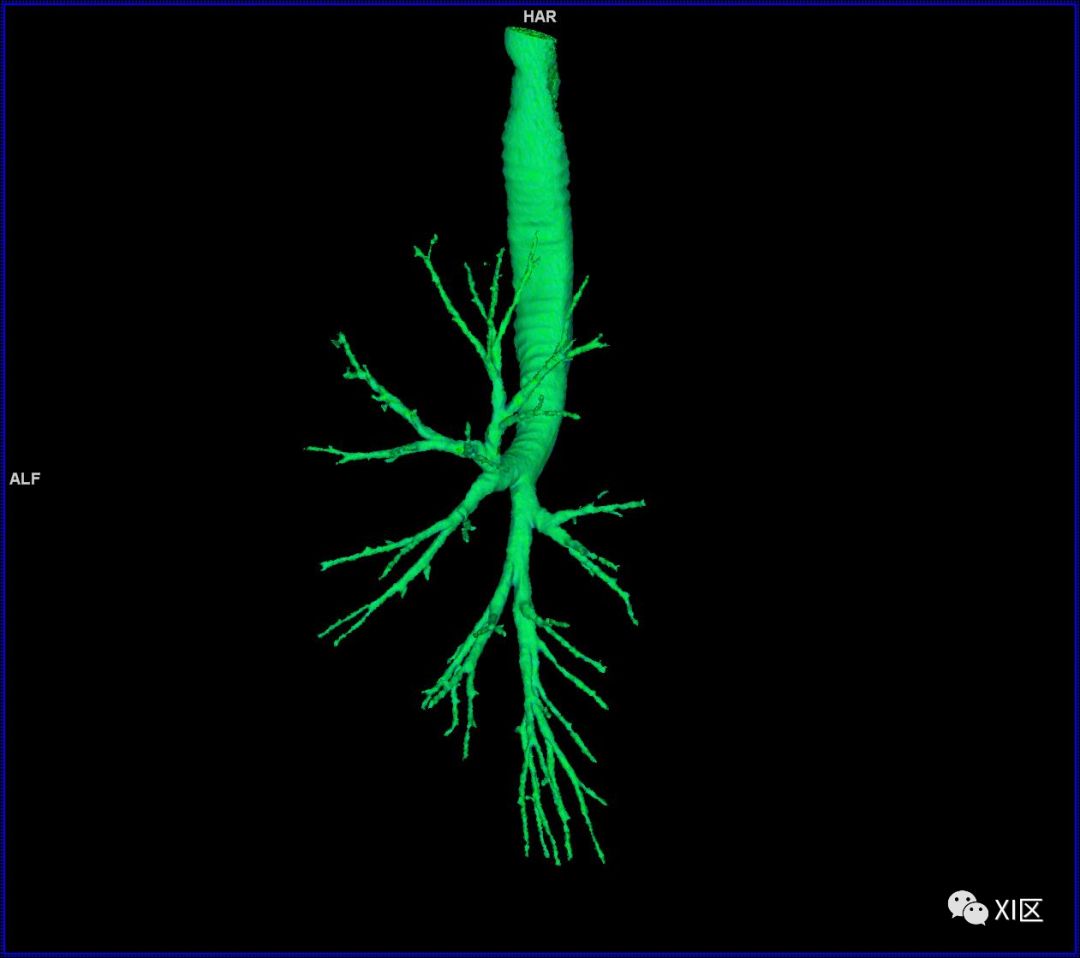

气管树的解剖

人的支气管(第1级)至肺泡约有24级分支。支气管经肺门入肺,分为叶支气管(第2级),右肺3支,左肺2支。叶支气管分为段支气管(第3~4级),左肺8支、右肺10支。段支气管就是肺的分段的依据。段支气管反复分支为小支气管(第5~10级),继而再分支为细支气管(第11~13级),细支气管又分支为终末细支气管(第14~16级)。从叶支气管至终末细支气管为肺内的导气部。终末细支气管以下的分支为肺的呼吸部,包括呼吸细支气管(第17~19级)、肺泡管(第20~22级)、肺泡囊(第23级)和肺泡(第24级)。

气管支气管形如树状,因此也称气管支气管树。

气管树